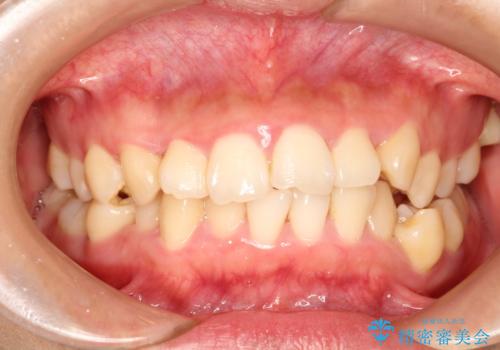

前歯のガタガタ / 歯の真ん中を揃える

- 八重歯、咬み合わせ不安定、上下正中のズレを主訴に来院。

初診時、他院による咬み合わせ治療として、不適切な詰め物がされている状態であった。

叢生および上下正中の改善のため、右上4番および右下5番の抜歯、審美装置とマイクロインプラントによる約2年の治療として、矯正治療を行った。

矯正治療による咬み合わせのリセット後(~6か月)、矯正を継続しながら適宜詰め物のやり替えをして歯を並べ(7~15カ月)、歯根の平行化を目的に微調整を行った(15~20か月)。